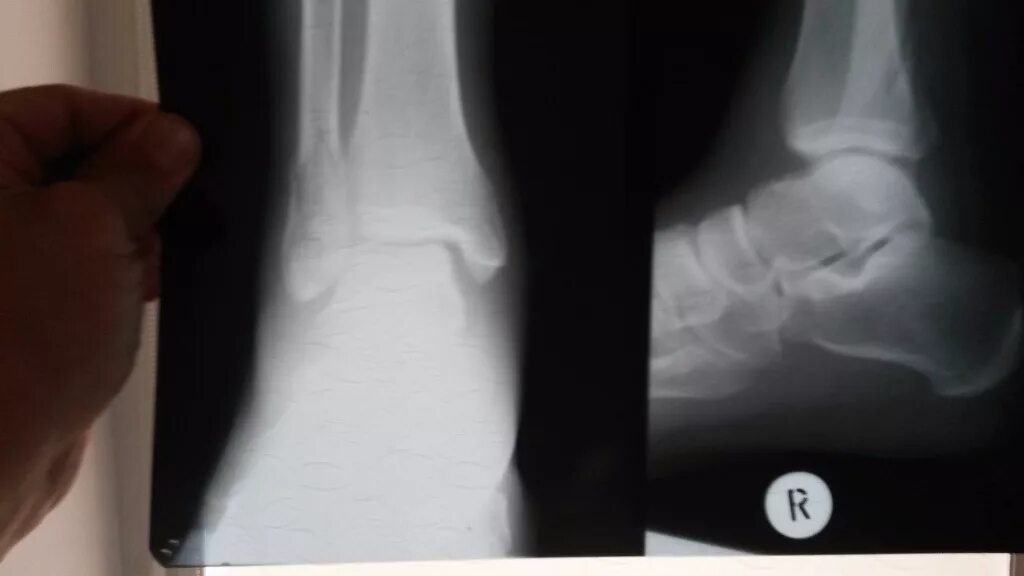

Срослась п и ж